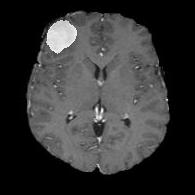

We first introduce a method for connecting the output of a CNN to an ACM, yielding a model for the precise delineation of lesions, to which we refer as Deep Active Lesion Segmentation (DALS) (Figure 4). We then go further to introduce a truly unified framework (Figure 5) that bridges the gap between ACMs and CNNs by leveraging a novel, automatically differentiable level-set ACM with trainable parameters that allows for back-propagation of gradients and can be end-to-end trained along with a backbone CNN from scratch, without any CNN pre-training. The ACM is initialized directly by the CNN and utilizes an energy functional that is locally-tunable by the backbone CNN, through 2D feature maps. Thus, our work overcomes the big hurdle of fully automating the powerful ACM approach to image segmentation. We have applied our proposed framework to the task of building segmentation in aerial images (Figure 6).

Deep Active Lesion Segmentation

[45]: Lesion segmentation is an important problem in computer-assisted diagnosis that remains challenging due to the prevalence of low contrast, irregular boundaries that are unamenable to shape priors. We introduce Deep Active Lesion Segmentation (DALS), a fully automated segmentation framework that leverages the powerful nonlinear feature extraction abilities of FCNs and the precise boundary delineation abilities of ACMs. Our DALS framework benefits from an improved level-set ACM formulation with a per-pixel-parameterized energy functional and a novel multiscale encoder-decoder CNN that learns an initialization probability map along with parameter maps for the ACM. We evaluate our lesion segmentation model on a new Multiorgan Lesion Segmentation (MLS) dataset that contains images of various organs, including brain, liver, and lung, across different imaging modalities—MR and CT. Our results demonstrate favorable performance compared to competing methods, especially for small training datasets. -